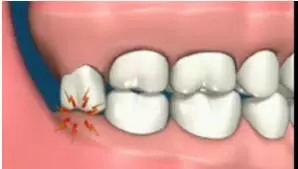

造成鄰牙病變

阻生智齒中典型的“秀恩愛,死得快”型,智齒因為萌出空間不足,造成傾斜阻生,斜靠在旁邊的牙齒上,把旁邊好好的鄰牙給直接頂壞掉。

640.webp (3).jpg

阻生智齒的幾種常見類型